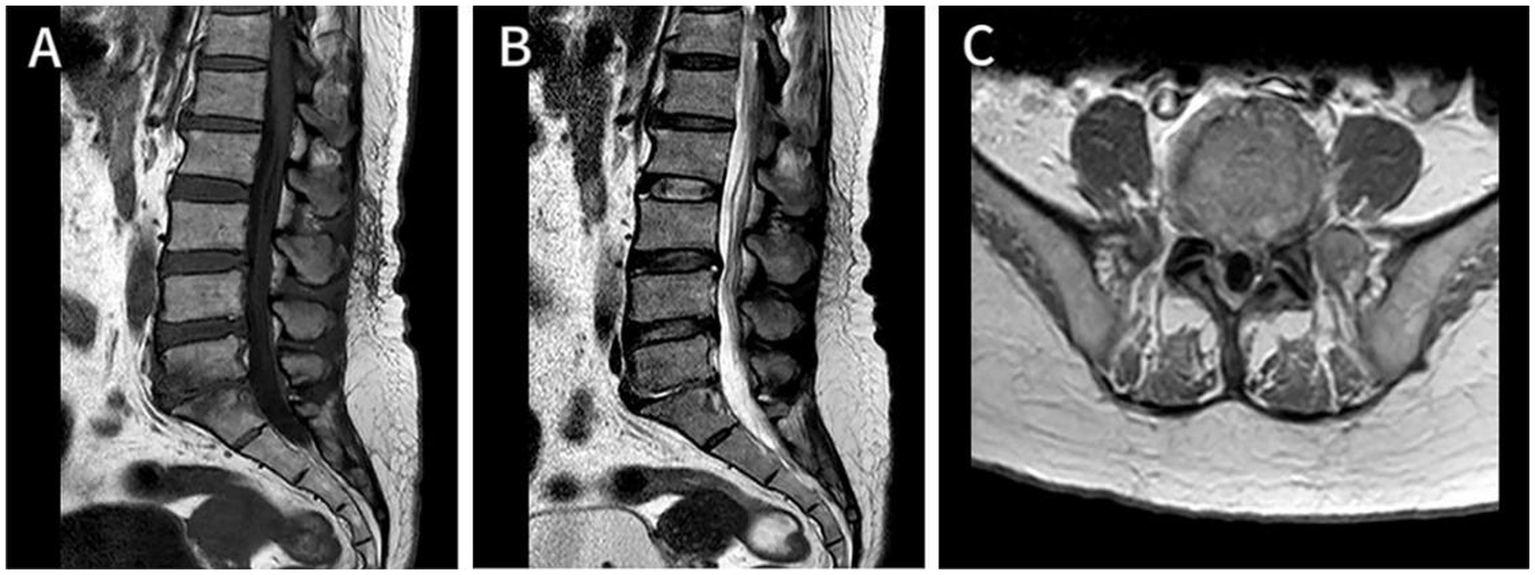

Figure 2

At 2-month follow-up, sagittal T1-weighted (A) and T2-weighted image (B) and showed the lumbar disc herniation was still present, and the epidural space in the posterior lumbar and anterior sacrococcygeal segments was wider than before, and the enhancement of the dural sac improved after enhancement compared with before. Axial T1-enhanced image (C) showed the previously large range of irregular non-enhanced areas has decreased compared to Figure 1F.

Figure 3

At 1.5-year follow-up, Axial T1-enhanced image of the cervical (A), thoracic (B), and lumbar (C) segments demonstrated that the epidural abscess was almost completely absorbed, and the epidural space now shows normal signal intensity, with a largely improved corresponding spinal cord compression.